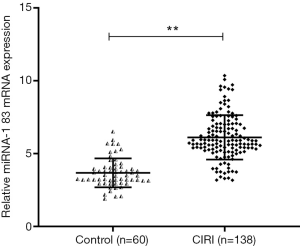

Enzyme-linked immunosorbent assay (ELISA) methods

The whole blood of each group of patients was collected with heparin for anticoagulation treatment, mixed and placed on ice, centrifuged at 4 °C at about 1,000–2,000 g for 10 minutes, and the light yellow supernatant was taken to obtain plasma. Using an ELISA kit (Beyotime Biotechnology Co., Ltd., China), the levels of TNF-α, IL-18, IL-1β and IL-6 in the supernatant were determined according to the instructions. Add samples or standards of different concentrations to the corresponding wells at 100 µL/well, seal the reaction wells with sealing film, incubate at room temperature for 120 minutes, wash the plate 5 times; add 100 µL/well of biotinylated antibody, and seal with sealing film Hold the reaction well, incubate at room temperature for 60 minutes, wash the plate 5 times; add horseradish peroxidase labeled Streptavidin 100 µL/well. Seal the reaction wells with a sealing film, and incubate for 20 minutes at room temperature in the dark. After incubation, wash the plate 5 times; add 100 µL/well of the developer TMB solution, seal the reaction wells with a sealing film (white), and incubate at room temperature away from light for 20 minute. Add 50 µL/well of stop solution, and measure the absorbance value at 450 nm after mixing.

The expression of TNF-α, IL-6, IL-8, and IL-1β in serum was upregulated

We used ELISA to detect the expression of inflammatory factors in serum. Compared with the control group, the serum levels of TNF-α, IL-6, IL-8, and IL-1β in the CIRI group were significantly higher (P<0.05) (Figure 3).

The inflammatory response also participates in the injury stage of cerebral ischemia-reperfusion. The aggregation and infiltration of neutrophils are particularly critical in the inflammatory response stage. The inflammatory response generates a release of various cytokines activated by vascular endothelial cells, platelets, and immune cells. During the progression of ischemia-reperfusion, inflammatory cells produce various cytokines, such as TNF-α, IL-1β, IL-6, IL-8, and others (23). In this study, we found that TNF-α, IL-6, IL-8, and IL-1β levels of CIRI patients increased compared with the those of control group, which confirmed the mechanism of vascular endothelial cell inflammatory injury in CIRI patients. We also revealed that the occurrence of CIRI was closely correlated to the expression levels of inflammatory cytokines, and that IL-1β could regulate the immune response produced in macrophages, T cells, B cells and other cells. This in turn increases the release of cell adhesion molecule-1, leading to improved adhesion of white blood cells and aggravating the inflammatory response and the nerve damage. TNF-α can stimulate the production of macrophages, resulting in an increased inflammatory response in the body and a more severe condition. The inflammatory cytokines produced by macrophages need the assistance of IL-1β, and both inflammatory cytokines are highly expressed and aggravate local inflammation. IL-8 is a cytokine that plays a chemotactic role in the body’s immune response and stress response, and the aggregation of inflammatory cells in the infarct area is intensified by the combined action of the above inflammatory factors (24). Studies have found that anti-IL-8 antibody can intervene in tissue damage caused by neutrophils and reduce the infarct area, suggesting that anti-IL-8 antibody may be a key measure in preventing tissue damage and inflammatory response. Zhou et al. (25) found scalp acupuncture can make the inflammatory cytokines TNF-α and IL-1β levels drop, and that IL-1β obvious inhibited leukocyte infiltration after cerebral ischemia reperfusion. Scalp acupuncture can protect the brain tissue injured by CIRI, accelerate the recovery of neural function after cerebral ischemia, and rebuild structural damage in nerve tissue. Deng tested TNF-α and IL-6 in a model and sham operation group by establishing a large CIRI model, and found that the levels of TNF-α and IL-6 in the model group were higher than those in the sham operation group. After the treatment with an alcohol extract of Radix Morindae Officinalis, the expressions of TNF-α and IL-6 were significantly reduced, which had a significantly protective effect on CIRI in rats. At present, the role and mechanism of miR-183 in CIRI has not been deeply studied. In addition to the inflammatory response, miR-183 is closely related to CIRI. Thus to clarify the diversity of expression of miR-183 in CSVD CIRI, a multi-direction study was carried out on miR-183 to provide a new research basis for the prevention and treatment of CIRI.